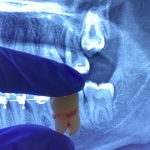

Operasi Gigi Bungsu/cabut gigi impaksi: Gigi bungsu yang tumbuh tidak normal atau impaksi (terdiri dari posisi miring atau tertanam sebagian di dalam gusi atau tulang) memerlukan prosedur yang lebih kompleks. Dokter gigi perlu membuat sayatan di gusi dan, dalam beberapa kasus, mungkin perlu memotong tulang untuk mengeluarkan gigi tersebut.

Operasi Gigi Bungsu: Lebih rumit dan bisa memakan waktu lebih lama, karena melibatkan pengangkatan gigi yang biasanya tertanam dalam gusi atau tulang.